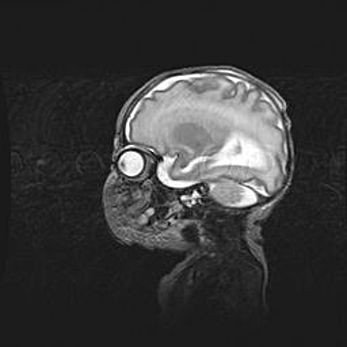

Церебральная ишемия II.

Возраст: 5 дней

Вес: 3400 г

Пол: женский

Окружность головы: 35 см

Срок гестации: 39 недель

Церебральная ишемия – это заболевание, характеризующееся недостаточностью (гипоксией) либо полным прекращением (аноксией) снабжения мозга кислородом по причине закупорки одного или нескольких сосудов. Это приводит к  что метаболическим расстройствам различной степени тяжести в тканях головного мозга, развитию коагуляционных некрозов и гибели нейронов.